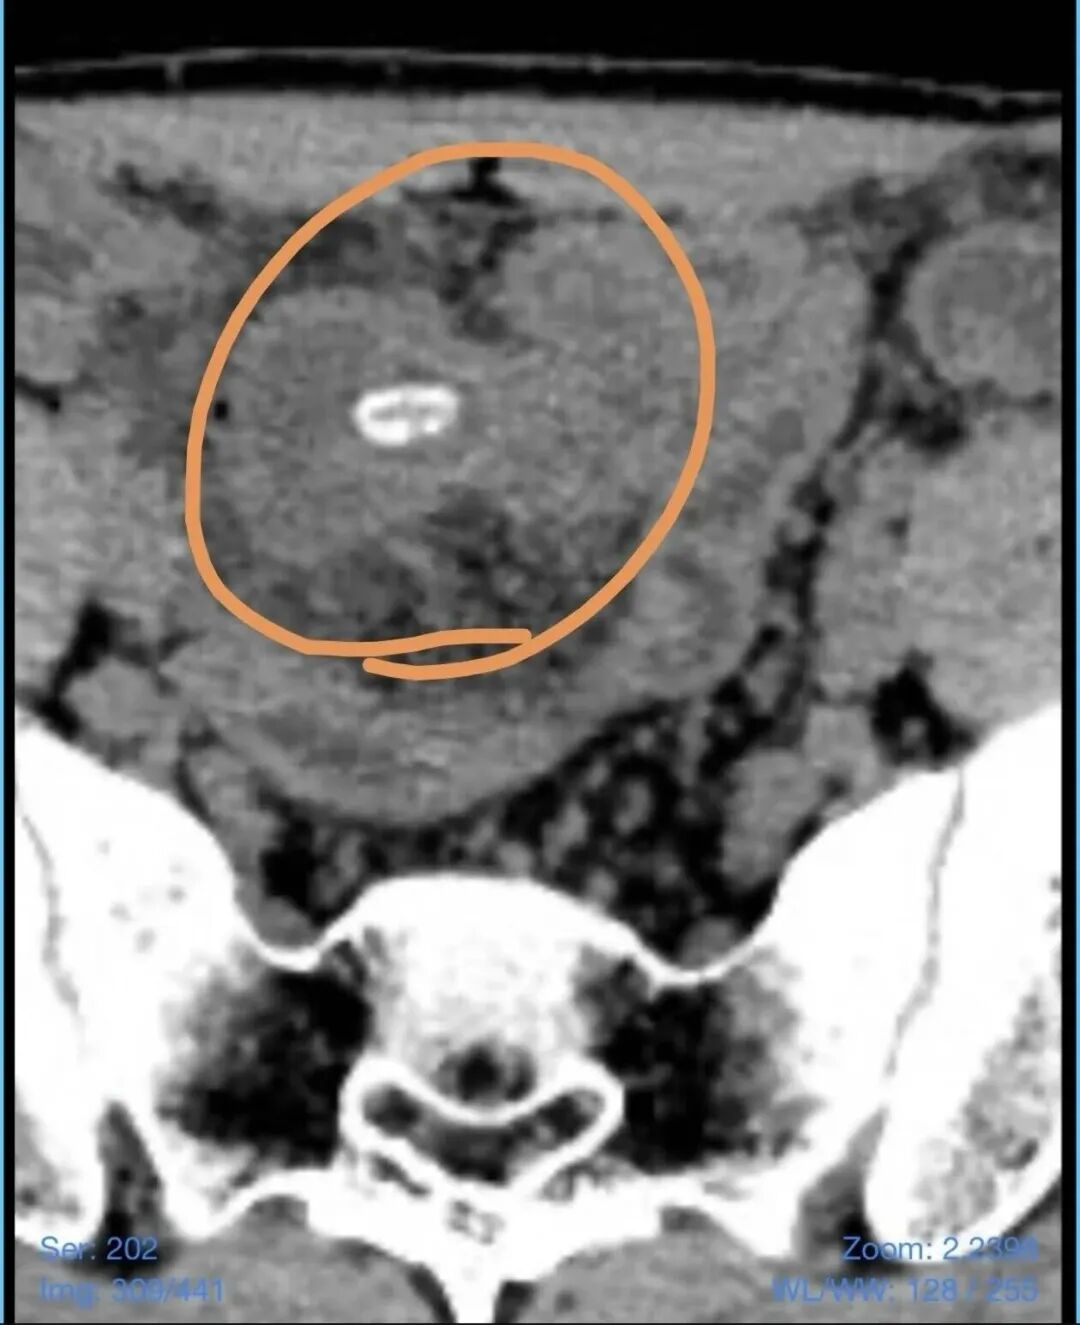

几天前,正在就读大学的小李(化名)突然感到右下腹持续性疼痛,有时甚至疼得直不起腰,无法正常活动。家人见状,立即将他送往附近医院就诊。腹部CT检查提示,小李的阑尾略增粗,同时小肠内竟有一个疑似坚果的异物影像。结合症状,接诊医生初步诊断为“阑尾炎”,并给予了抗感染保守治疗。

结合患者右下腹持续加重的疼痛、腹部明显的压痛反跳痛等体征,以及CT提示的小肠内异物,夏伟凭借丰富的临床经验,敏锐地意识到这并非普通的阑尾炎。“患者的症状虽然很像阑尾炎,但抗感染治疗无效,这提示我们病因可能更为复杂。”夏伟分析道,“我们高度怀疑是瓜子导致了‘美克尔憩室’这一先天性肠道畸形部位的穿孔。”

术中所见证实了夏伟的判断。腹腔镜下,清晰可见小李回肠末端有一个先天性的憩室,而该憩室的顶端已经发生糜烂穿孔,穿孔周围积聚了大量脓液,周围肠管水肿充血明显,腹腔内已出现局限性腹膜炎。手术团队精细操作,小心分离粘连组织,最终将病变的憩室完整切除。当切开切除的标本时,所有人都不禁倒吸一口凉气——在憩室内,赫然躺着一枚完整的、未被消化的瓜子。

正是这枚被整个吞下的瓜子,随着肠道蠕动,恰好嵌顿在了这个名为“美克尔憩室”的薄弱“口袋”里,日复一日地刺激、磨损黏膜,最终导致憩室穿孔,引发了这一场惊心动魄的急腹症。